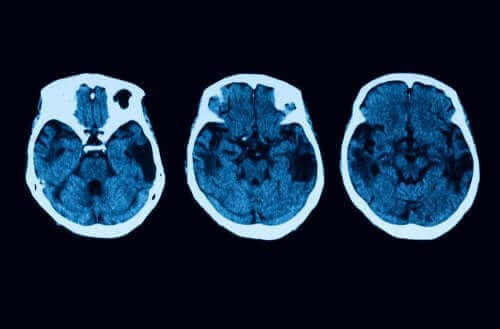

- Начало на деменция: Човек с това заболяване ще показва хипометаболизъм и хипоперфузия, които могат да бъдат проследени благодарение на изследване, което се състои от невровизуално изследване. Имайте предвид, че деменцията възниква когато болестта е сравнително напреднала.

Но, диагностичните изследванията не свършват до тук. За да се освободите от всякакви съмнения, ще има неврологични изследвания като например ЯМР и томографии. Ако всичко показва, че бихте могли да имате задна кортикална атрофия, тогава има различни начини на лечение, които бихте могли да предпочетете.